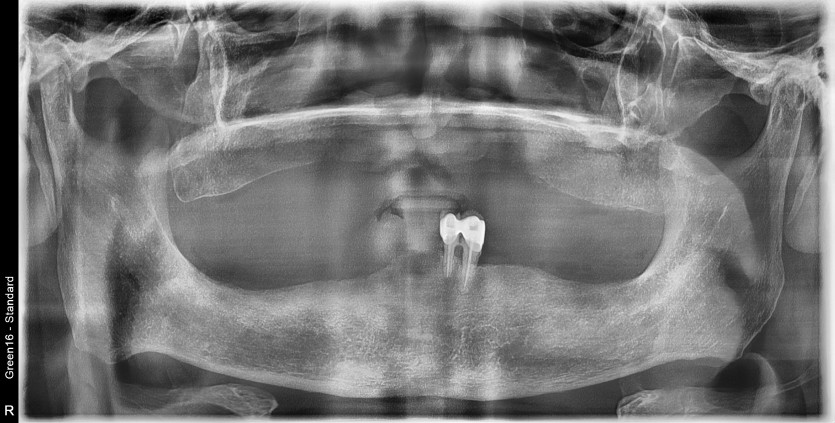

전체 임플란트 증례입니다.

18개의 임플란트로 완성하였습니다.